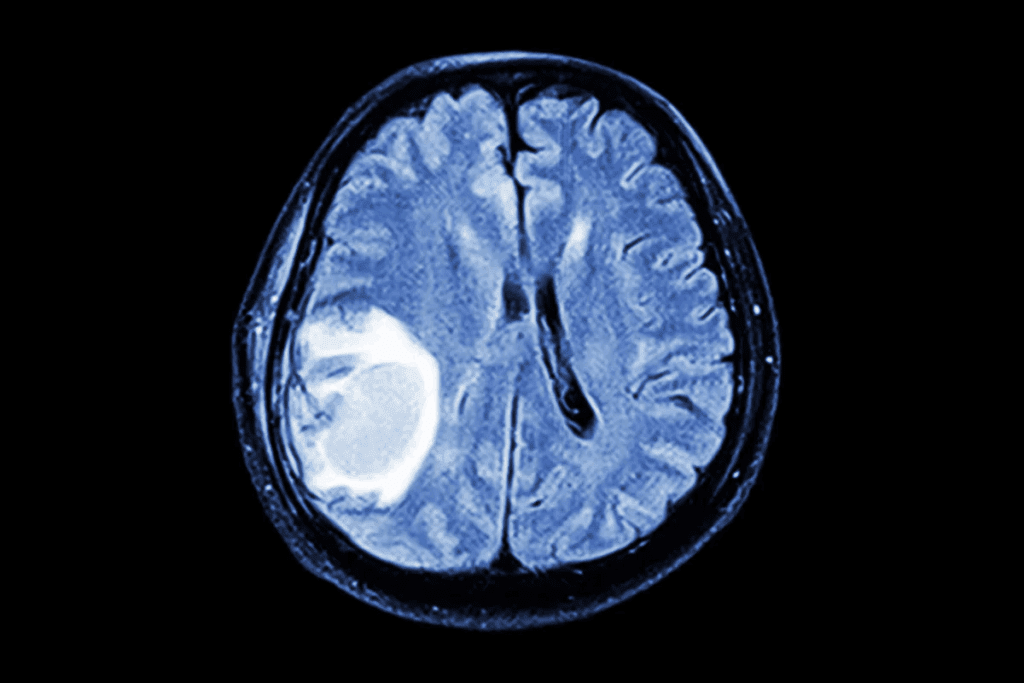

Diagnostic Approaches for Metastatic Brain Tumors

Diagnosing metastatic brain tumors requires imaging, biopsies, and molecular tests. Getting the diagnosis right is key for good treatment plans.

Imaging Techniques

Imaging is vital for spotting metastatic brain tumors. The main tools used are:

- Magnetic Resonance Imaging (MRI): MRI is top-notch for finding brain metastases, thanks to contrast agents like gadolinium.

- Computed Tomography (CT) scans: CT scans are faster and easier to get than MRI but miss smaller metastases.

- Positron Emission Tomography (PET): PET scans, paired with CT or MRI, offer metabolic insights into tumors.